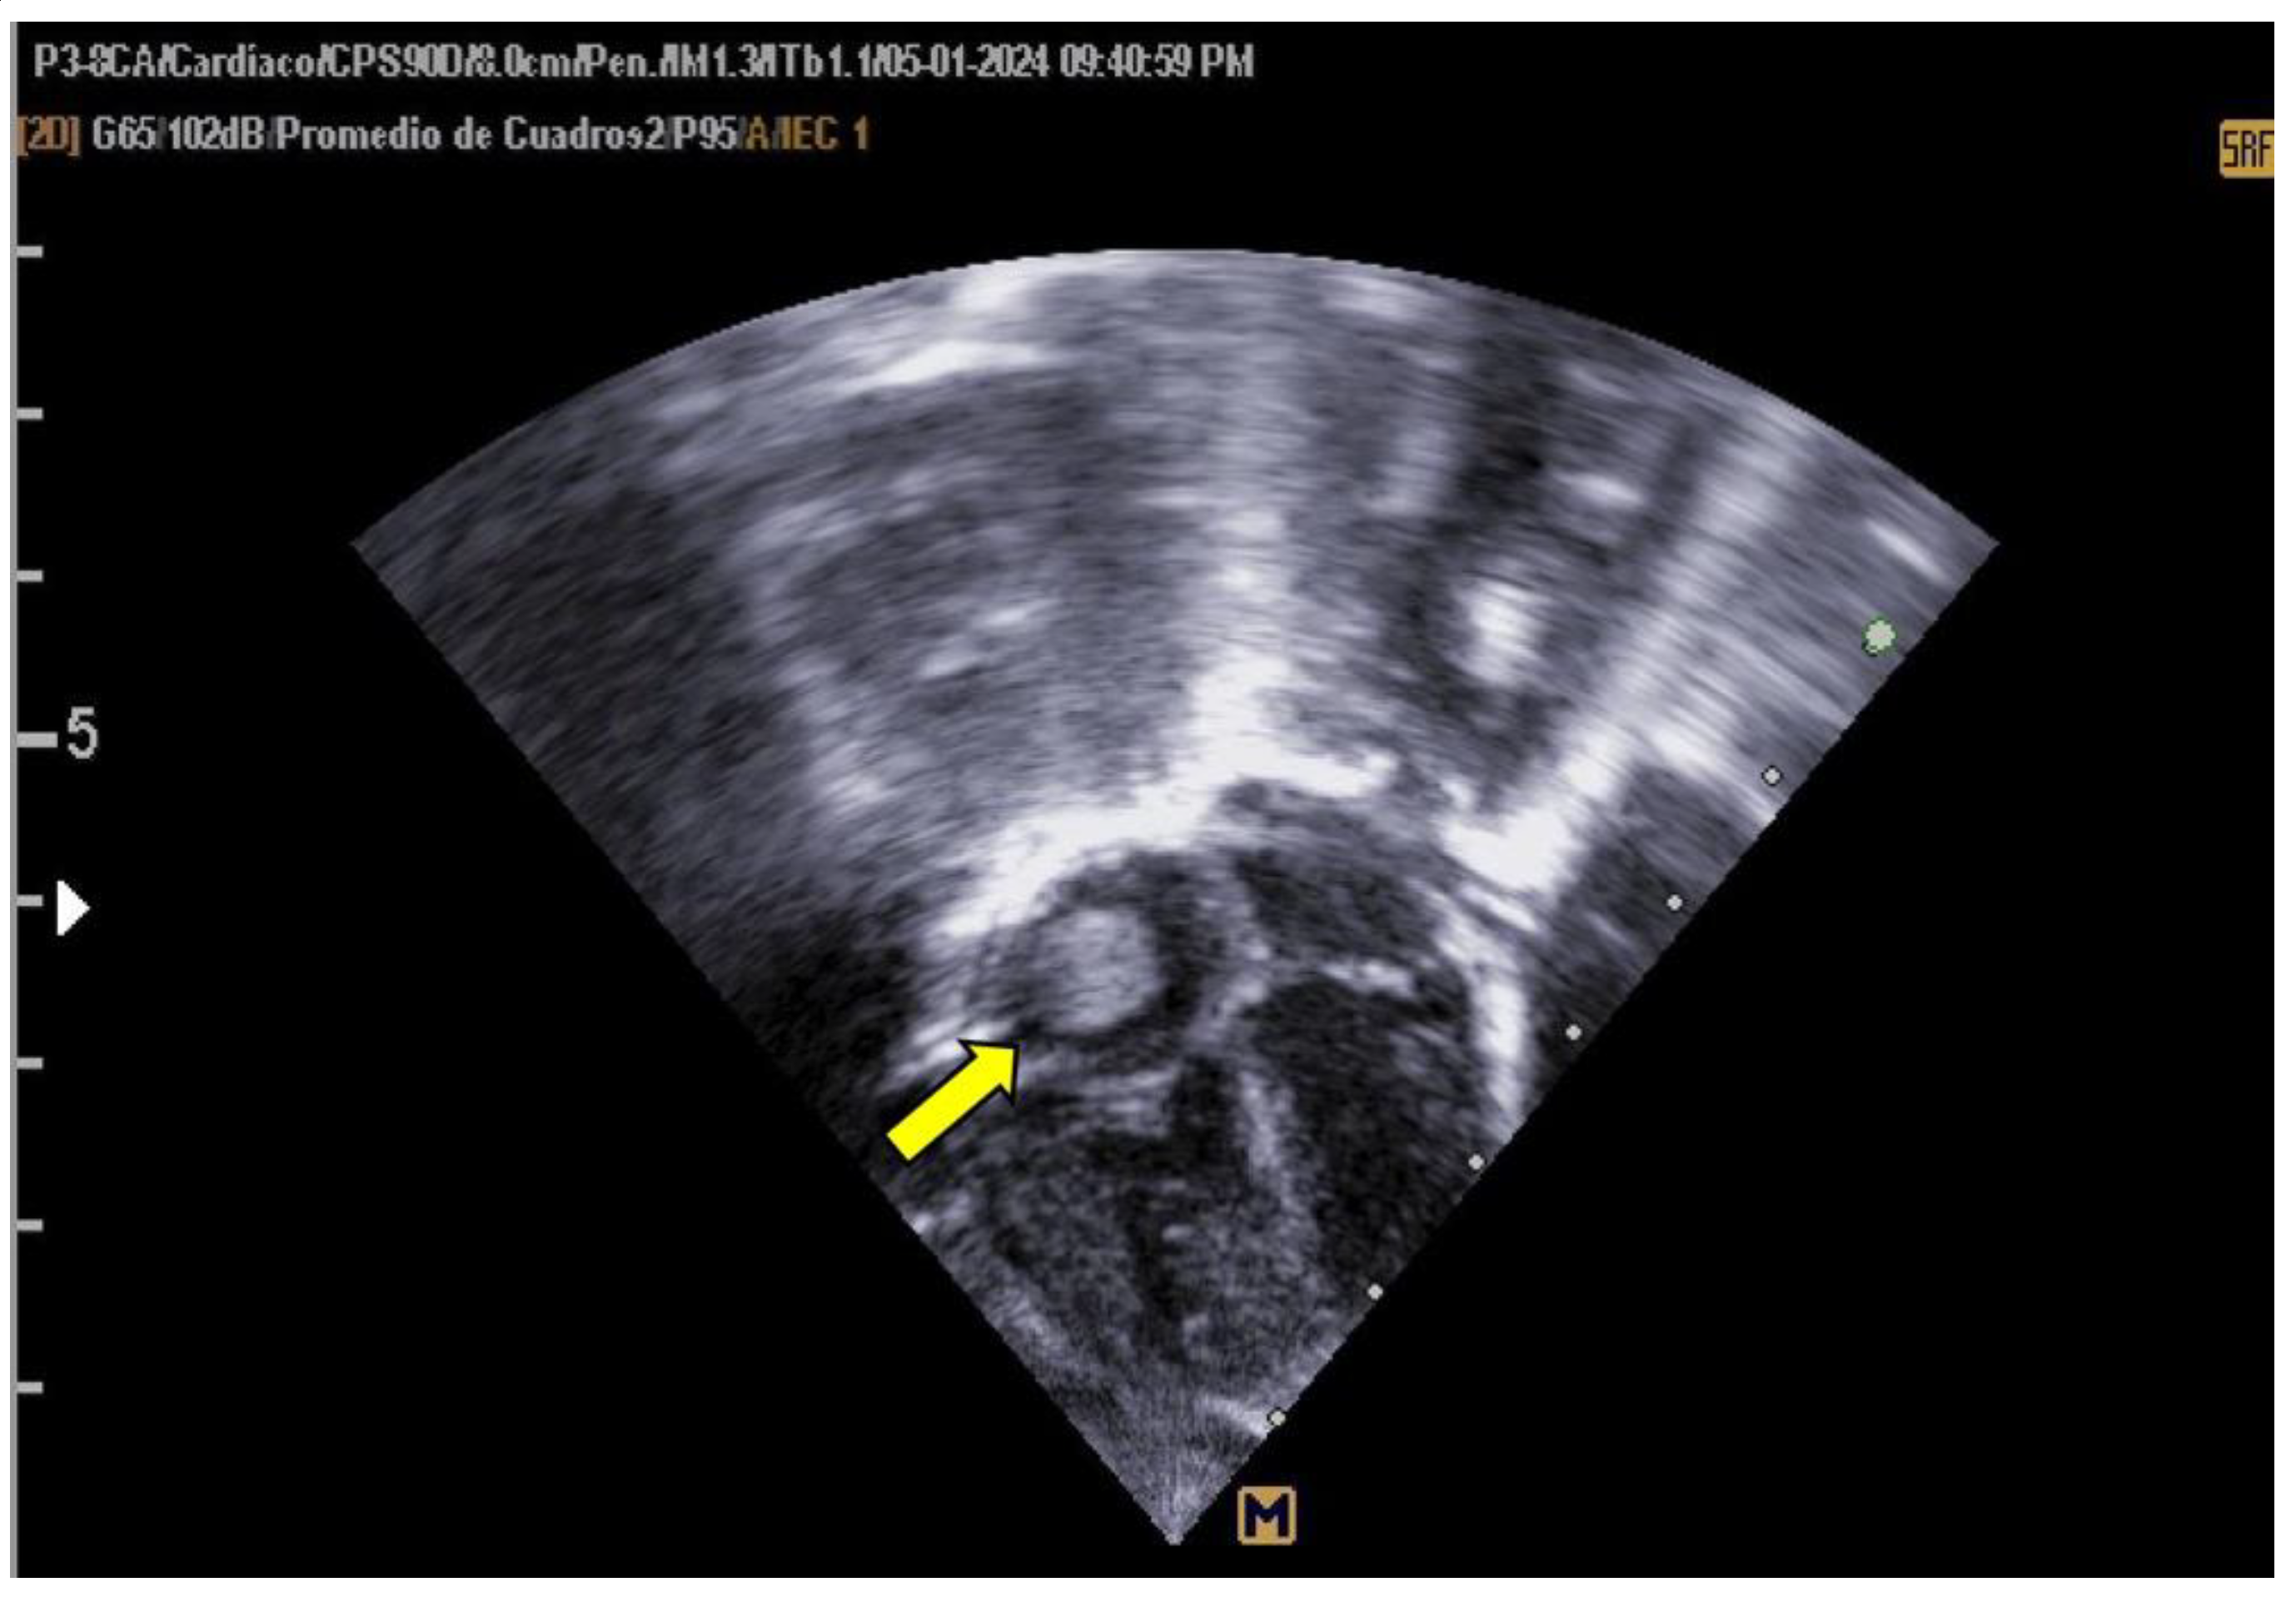

The patient was monitored weekly by a pediatric cardiologist. Despite no reduction in thrombus size during follow-up, the thrombus remained well-attached and non-pendulous, with no immediate indication for thrombolytic therapy. Due to the high risks associated with prolonged hospitalization, reinfection, and potential bleeding, the patient was discharged to avoid further complications. The family was counseled on embolization risks, and outpatient management with aspirin (AAS) was initiated. Follow-up evaluations were conducted weekly for two months and subsequently on a monthly basis. Complete thrombus resolution was observed by the sixth month, as illustrated in Figure 2.

Figure 2. Transthoracic Echocardiogram, Apical 4-Chamber View Complete resolution of the interatrial thrombus.